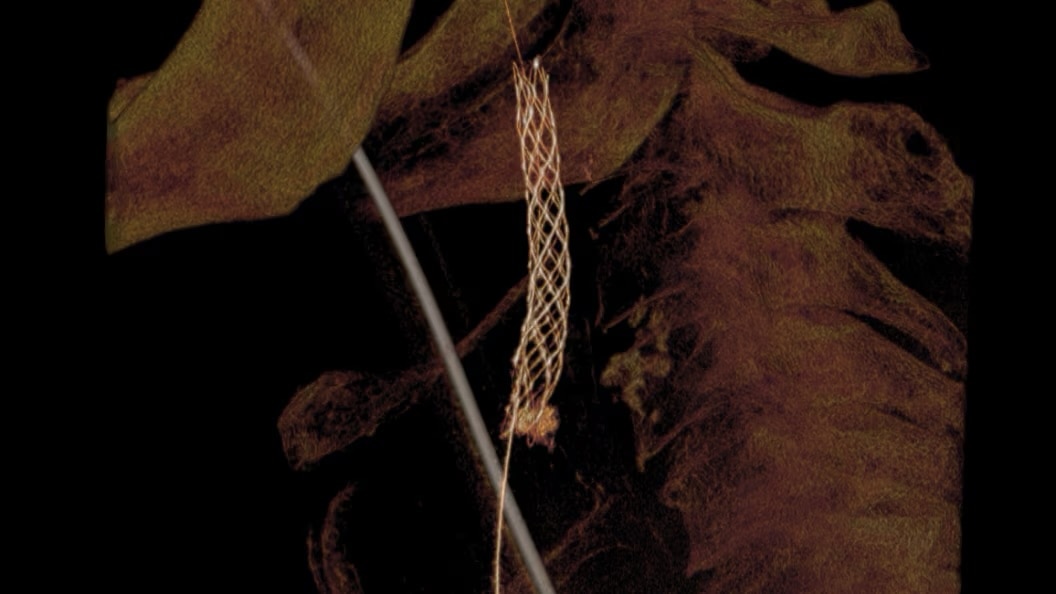

EVAR ASSIST

Perform endograft procedures in one go with intuitive tools and a simplified workflow - less radiation, more efficiency